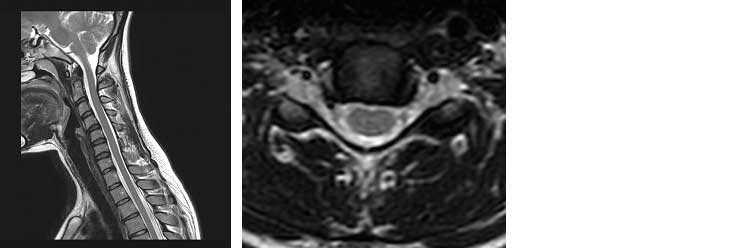

Lo studio della colonna cervicale, dorsale e lombo-sacrale risulta l’esame più richiesto in risonanza magnetica in quanto permette una ottima identificazione delle patologie discali erniarie. L’esame permette altresì una perfetta valutazione del midollo spinale. Grazie a sequenze T2 STIR è possibile evidenziare fratture vertebrali recenti.